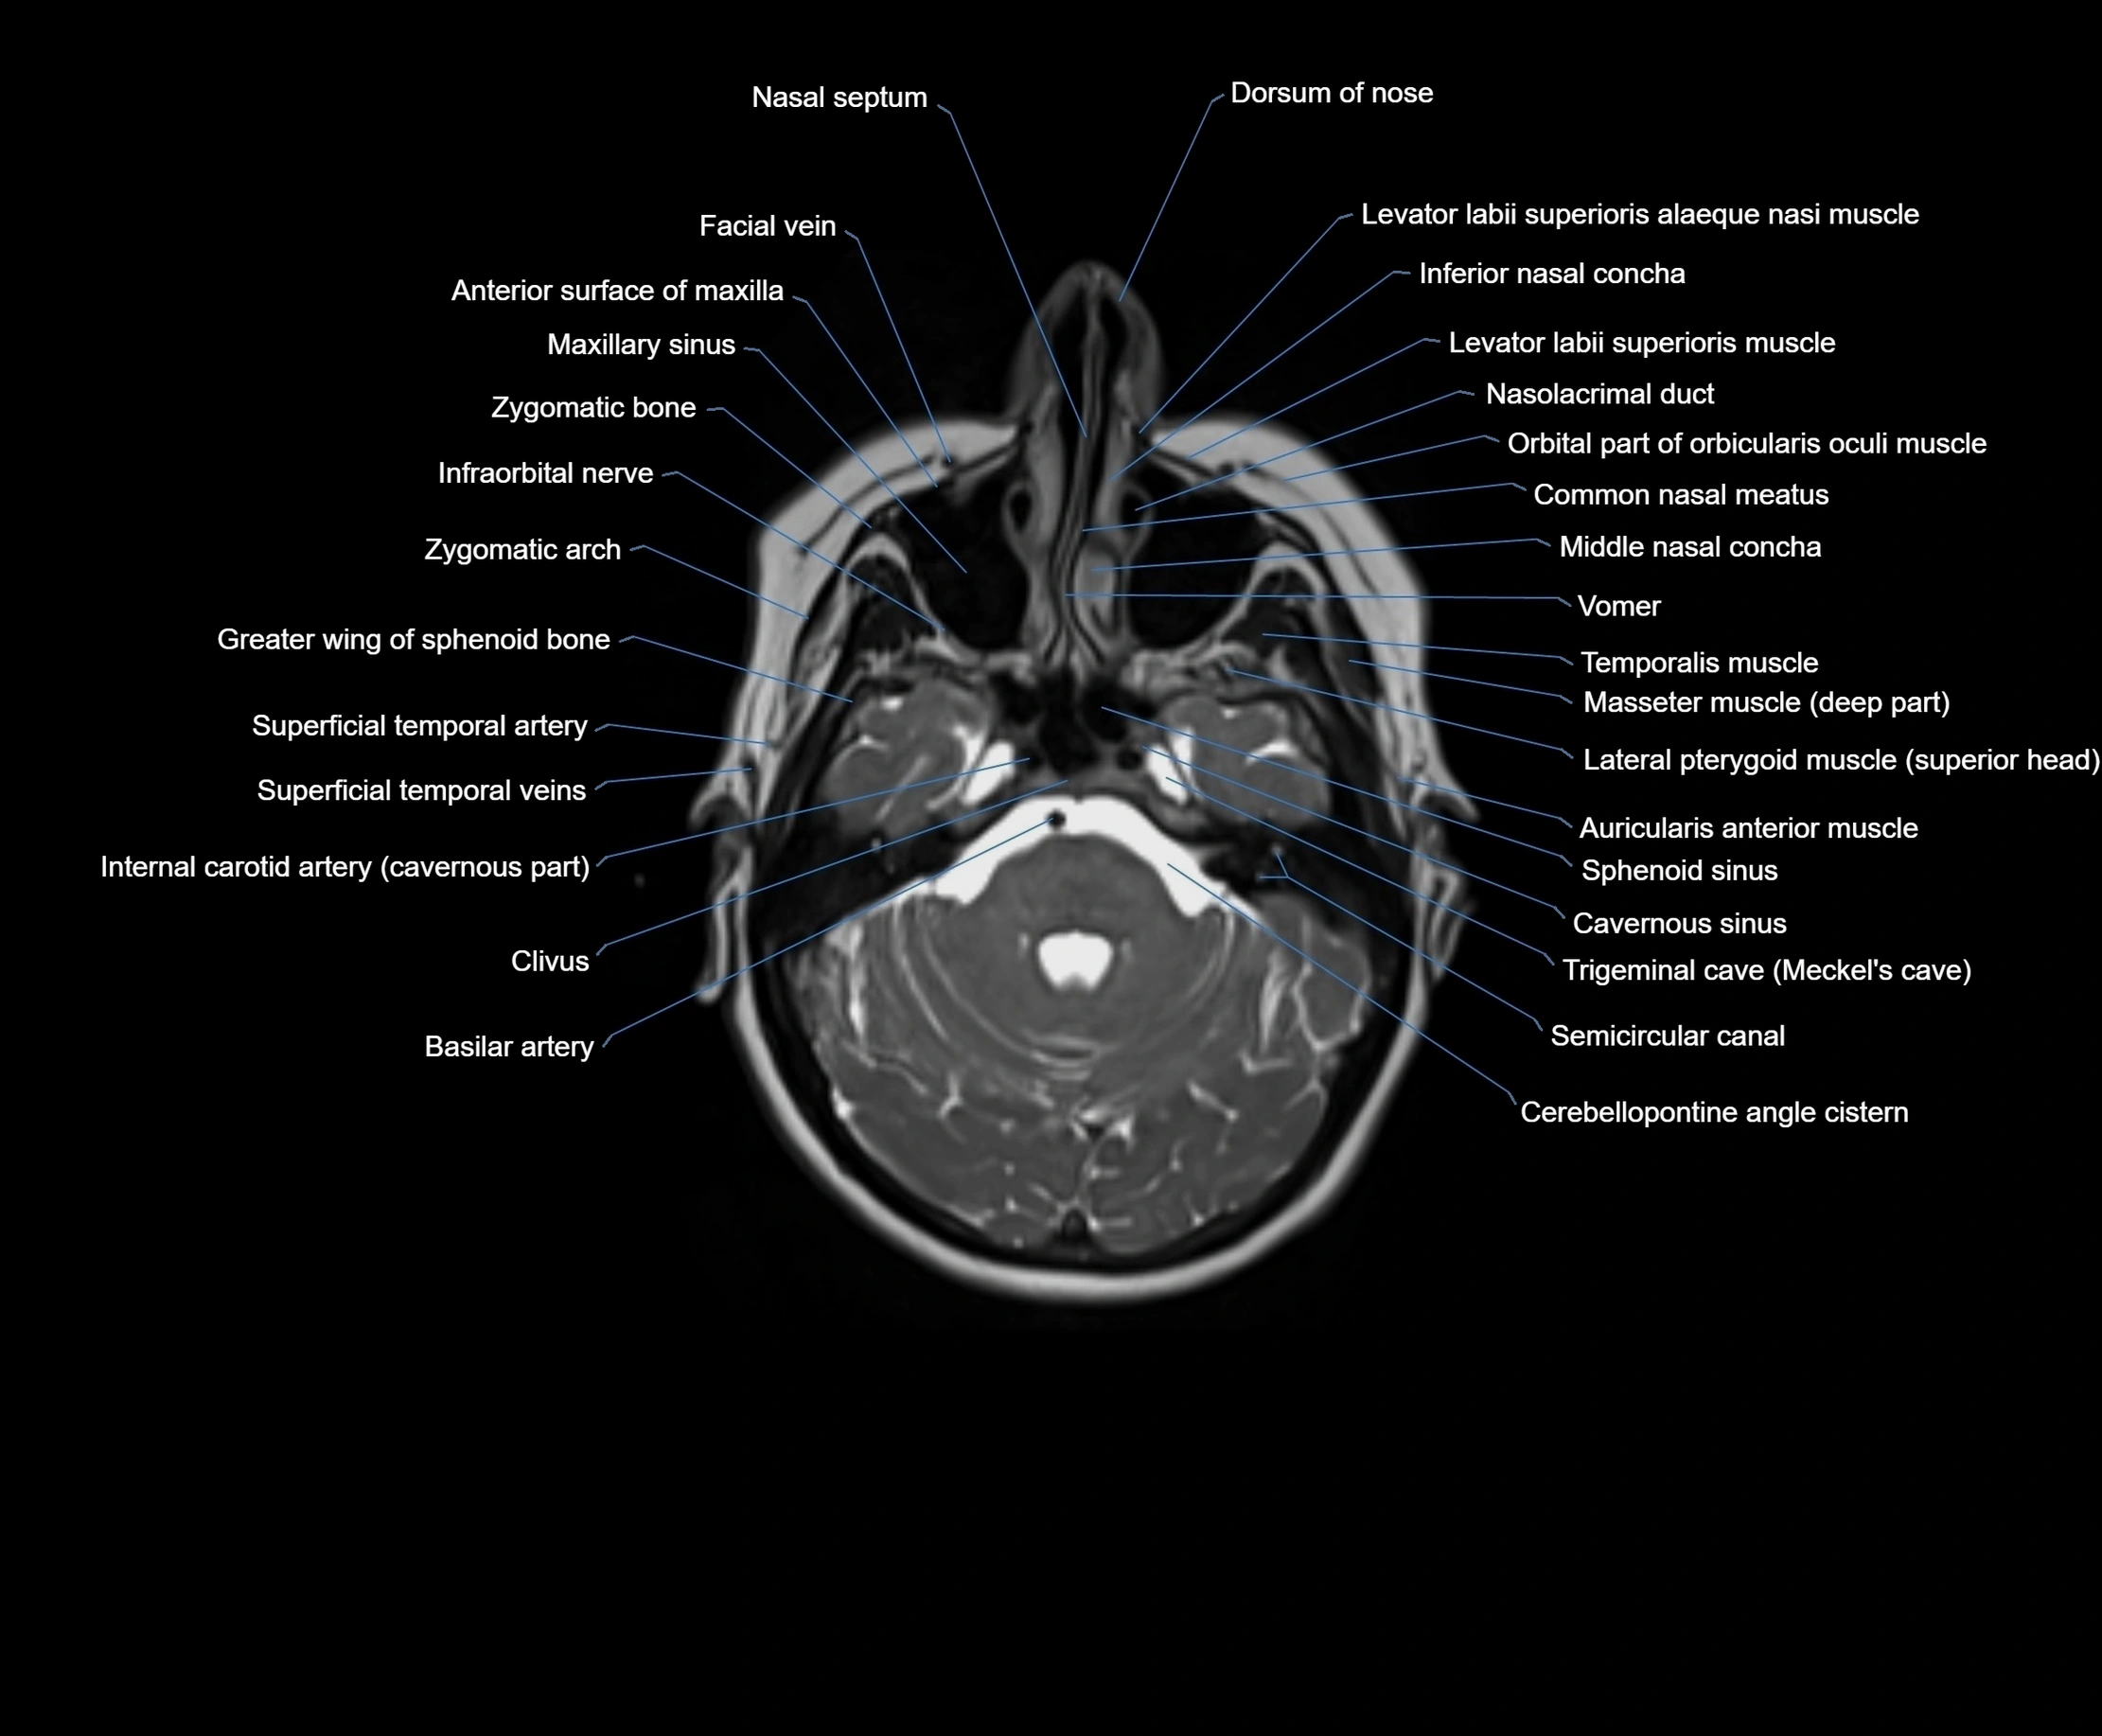

MRI images